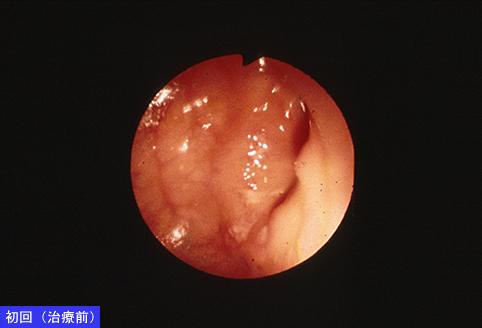

症例提示(所在地,施設名等): 東京都・ 国立がんセンター中央病院と九州がんセンターの共同作成

症例登録日 2004/05/31

画像数 24

性別 女性

年齢 55-59

取得年代 1980-1984

画像ID:7341

疾患(病理主体)の分類炎症性・潰瘍性疾患/結核

部位(臓器別)大腸/上行

検査方法内視鏡

病変の最大径(ミリ)1〜9